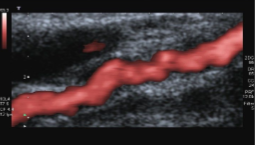

What is seen in this image?

How will the sonographer doppler this image?

Accessory renal arteries

Doppler each one